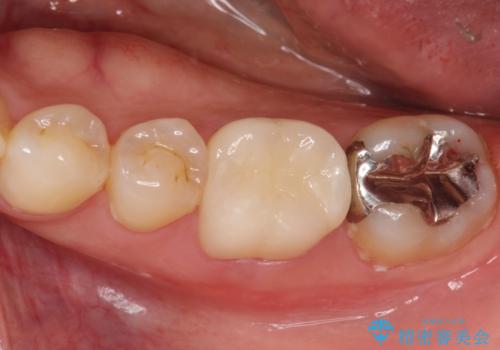

【根管治療】噛んだ時にしみる。最近になってズキズキ痛み、長引く痛みがある

担当医 河口智英